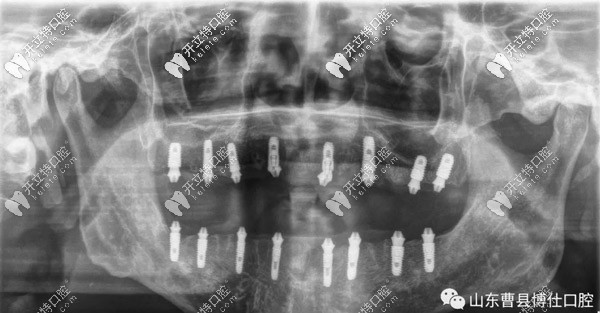

經(jīng)過(guò)一個(gè)半小時(shí)的手術(shù)時(shí)間,徐大爺上頜和下頜各植入8顆種植體,縫合傷口后,拍片顯示植入位置非常好。

通過(guò)拍片顯示,臨時(shí)牙和螺栓結(jié)合非常緊密,不需要調(diào)整,也經(jīng)過(guò)多次的反復(fù)咬合之后,并沒(méi)有不適的情況。